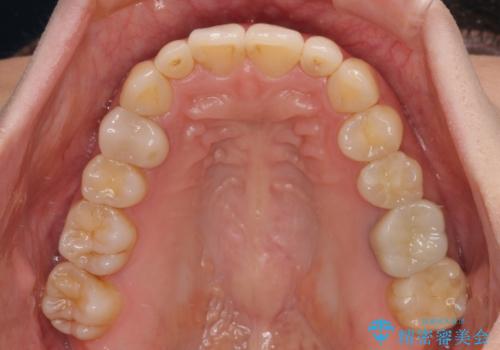

- 上顎前歯の突出感を気にして来院された患者様です。

下顎前歯2本が先天欠損しており、上顎歯列に対して、下顎歯列がアンバランスに小さい状況でした。

左右上顎側切歯2本が矮小歯であるため、上顎の抜歯ではなく、IPR(歯と歯の間を削る)と歯列全体の後方移動によってバランスを整えることとしました。

歯列のバランスが悪く、インビザライン矯正特有の奥歯の噛みにくさがなかなか改善されず、治療期間が長期化してしまいました。